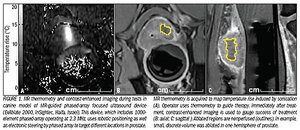

Focused ultrasound ablation offer prostate cancer option

ByClare Tempany, MD,Jalil Afnan, MD